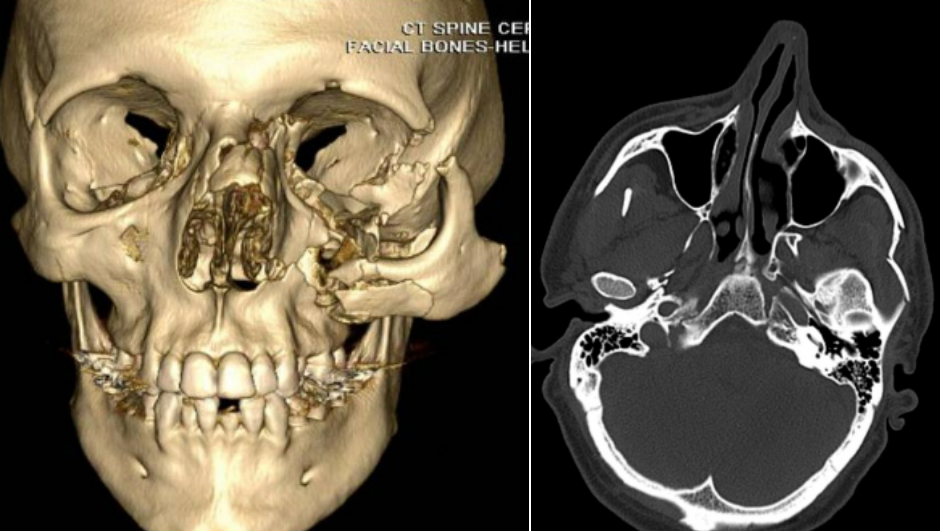

O exame padrão-ouro para o diagnóstico é a Tomografia Computadorizada (TC) de face com reconstrução 3D, que oferece uma visualização detalhada das estruturas ósseas nos planos axial, coronal e sagital.

- Fratura de Zigoma: O complexo zigomático-maxilar é fundamental para a projeção da região malar e a arquitetura da órbita. Fraturas podem causar afundamento do malar, distopia ocular (alteração na altura do globo ocular), lesão do nervo infraorbital e trismo por interferência com o processo coronoide da mandíbula. O tratamento cirúrgico é indicado quando há diástase significativa das suturas zigomático-frontal (ZF) ou zigomático-maxilar (ZM).

- Fratura de Maxila (Classificação de Le Fort): São fraturas de alto impacto que seguem padrões previsíveis, classicamente descritos por René Le Fort.

- Le Fort I: Fratura transversal que separa o processo alveolar do restante da maxila. Causa principalmente mal-oclusão.

- Le Fort II: Fratura piramidal que se estende da região pterigoide, através do assoalho da órbita, até a raiz do nariz.

- Le Fort III: Conhecida como disjunção craniofacial, representa uma separação completa entre os ossos da face e a base do crânio. Resulta em alongamento e retração da face. As fraturas Le Fort II e III podem estar associadas a fístula liquórica.